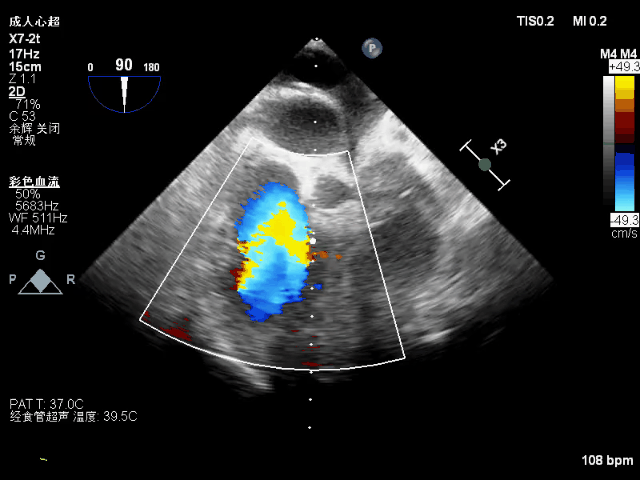

术后